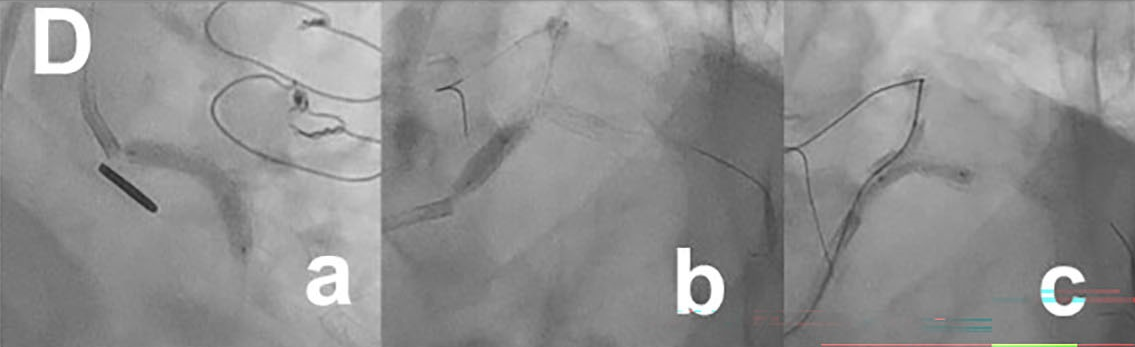

Since CCTA indicated a blunt-type LM chronic total occlusion (CTO) in the straight route that was composed of fibrous tissue and connected to distal bifurcation (Figure A), percutaneous coronary intervention (PCI) for LM-CTO was performed with contralateral injection from the LITA-LAD. A 7-French AL2.0 SH guide catheter (Heartrail II, Terumo) was engaged in the LM and a tapered stiff guidewire (X-treme XTA, Asahi Intec) penetrated the CTO lesion and crossed to the LCX (Video 3). Intravascular ultrasound confirmed the guidewire’s penetration of the true lumen. (Figure C; Video 4). A 3.5 x 22-mm zotarolimus-eluting stent (Resolute Onyx, Medtronic) was implanted from the LM ostium to the proximal LCX (Figure D-a). Proximal optimization with a 4.0-mm balloon (Figure D-b), and final kissing balloon inflation with 3.5 and 2.5-mm balloons (Figure D-c) followed. Complete antegrade flow from the LM to LCX and good collateral flow into the distal RCA was achieved (Figure E-a, b; Videos 5 and 6). The proximal to middle LAD lesions were left untouched due to sufficient flow from the LITA-LAD graft (Figure E-c). Informed consent was obtained from the patient prior to all procedures.